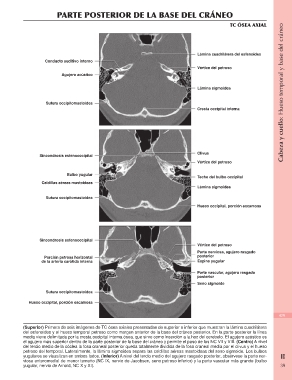

PARTE POSTERIOR DE LA BASE DEL CRÁNEO Cabeza y cuello: Hueso temporal y base del cráneo

TC ÓSEA AXIAL

Conducto auditivo interno Lámina cuadrilátera del esfenoides

Agujero acústico Vértice del petroso

Lámina sigmoidea

Sutura occipitomastoidea Cresta occipital interna

Sincondrosis esfenooccipital Clivus

Vértice del petroso

Bulbo yugular Techo del bulbo occipital

Celdillas aéreas mastoideas Lámina sigmoidea

Sutura occipitomastoidea Hueso occipital, porción escamosa

Sincondrosis esfenooccipital Vértice del petroso

Porción petrosa horizontal

Parte nerviosa, agujero rasgado

de la arteria carótida interna posterior

Espina yugular

Sutura occipitomastoidea

Hueso occipital, porción escamosa Parte vascular, agujero rasgado

posterior

Seno sigmoide

(Superior) Primera de seis imágenes de TC ósea axiales presentadas de superior a inferior que muestran la lámina cuadrilátera 429

del esfenoides y el hueso temporal petroso como margen anterior de la base del cráneo posterior. En la parte posterior la línea

media viene delimitada por la cresta occipital interna ósea, que sirve como inserción a la hoz del cerebelo. El agujero acústico es II

el agujero más superior dentro de la parte posterior de la base del cráneo y permite el paso de los NC VII y VIII. (Centro) A nivel

del tercio medio de la cóclea la fosa craneal posterior queda totalmente dividida de la fosa craneal media por el clivus y el hueso 39

petroso del temporal. Lateralmente, la lámina sigmoidea separa las celdillas aéreas mastoideas del seno sigmoide. Los bulbos

yugulares se visualizan en ambos lados. (Inferior) A nivel del tercio medio del agujero rasgado posterior, obsérvese la parte ner-

viosa anteromedial de menor tamaño (NC IX, nervio de Jacobsen, seno petroso inferior) y la parte vascular más grande (bulbo

yugular, nervio de Arnold, NC X y XI).